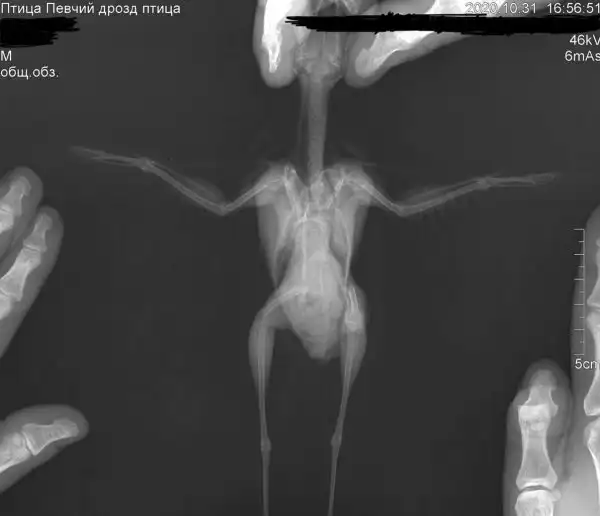

Рентген дрозда